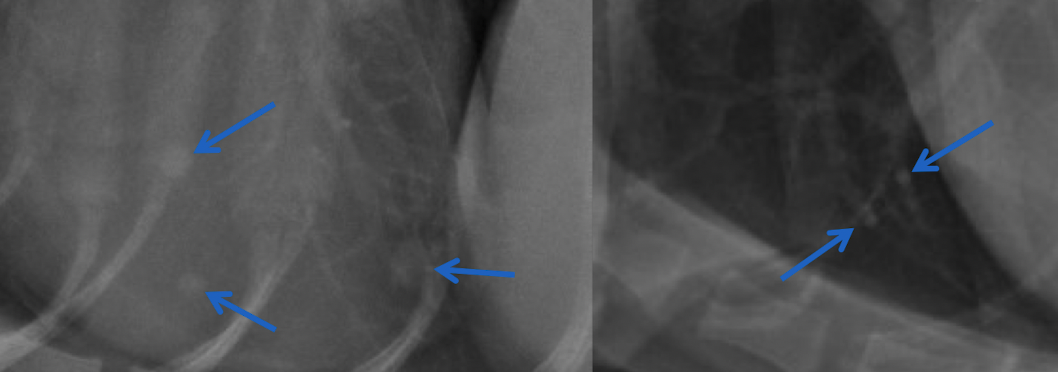

pumonary nodules or end on vessel

A

compare nodules